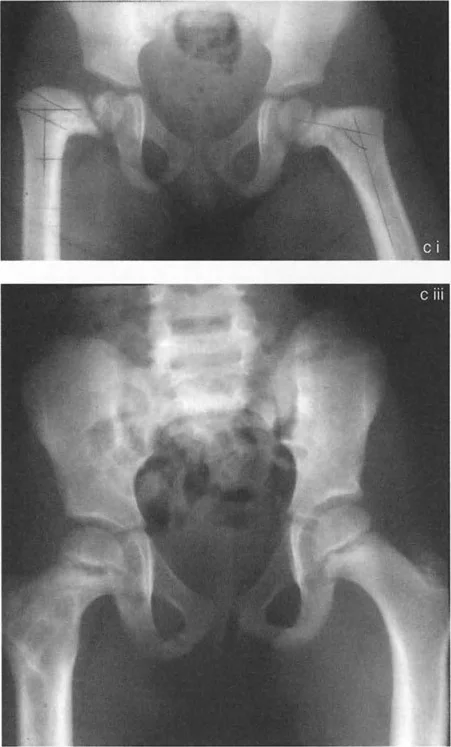

* الأشعة السينية (X-rays): هي الخطوة الأولى والأكثر شيوعًا. توفر صورًا مفصلة للعظام وتسمح بقياس الزوايا المهمة مثل زاوية عنق الفخذ (Neck-Shaft Angle - NSA) وزاوية محاذاة الفخذ القريبة (Proximal Femoral Alignment Angle - PFAA).

* التصوير المقطعي المحوسب (CT Scan): يوفر صورًا ثلاثية الأبعاد للعظام، وهو مفيد بشكل خاص لتقييم التشوهات المعقدة وتخطيط الجراحة بدقة.

يستخدم الدكتور هطيف قياسات دقيقة من الأشعة السينية لتحديد مدى التشوه:

* زاوية عنق الفخذ (NSA): الزاوية بين عنق الفخذ وجسم عظم الفخذ. تُشير قيمها المنخفضة إلى الورك الفحجاء، والعالية إلى الورك الروحاء.

جراحة عظم الفخذ الفحجاء (Valgus Osteotomy) لتصحيح الورك الفحجاء (Varus Deformity)

جراحة عظم الفخذ الروحاء (Varus Osteotomy) لتصحيح الورك الروحاء (Valgus Deformity)